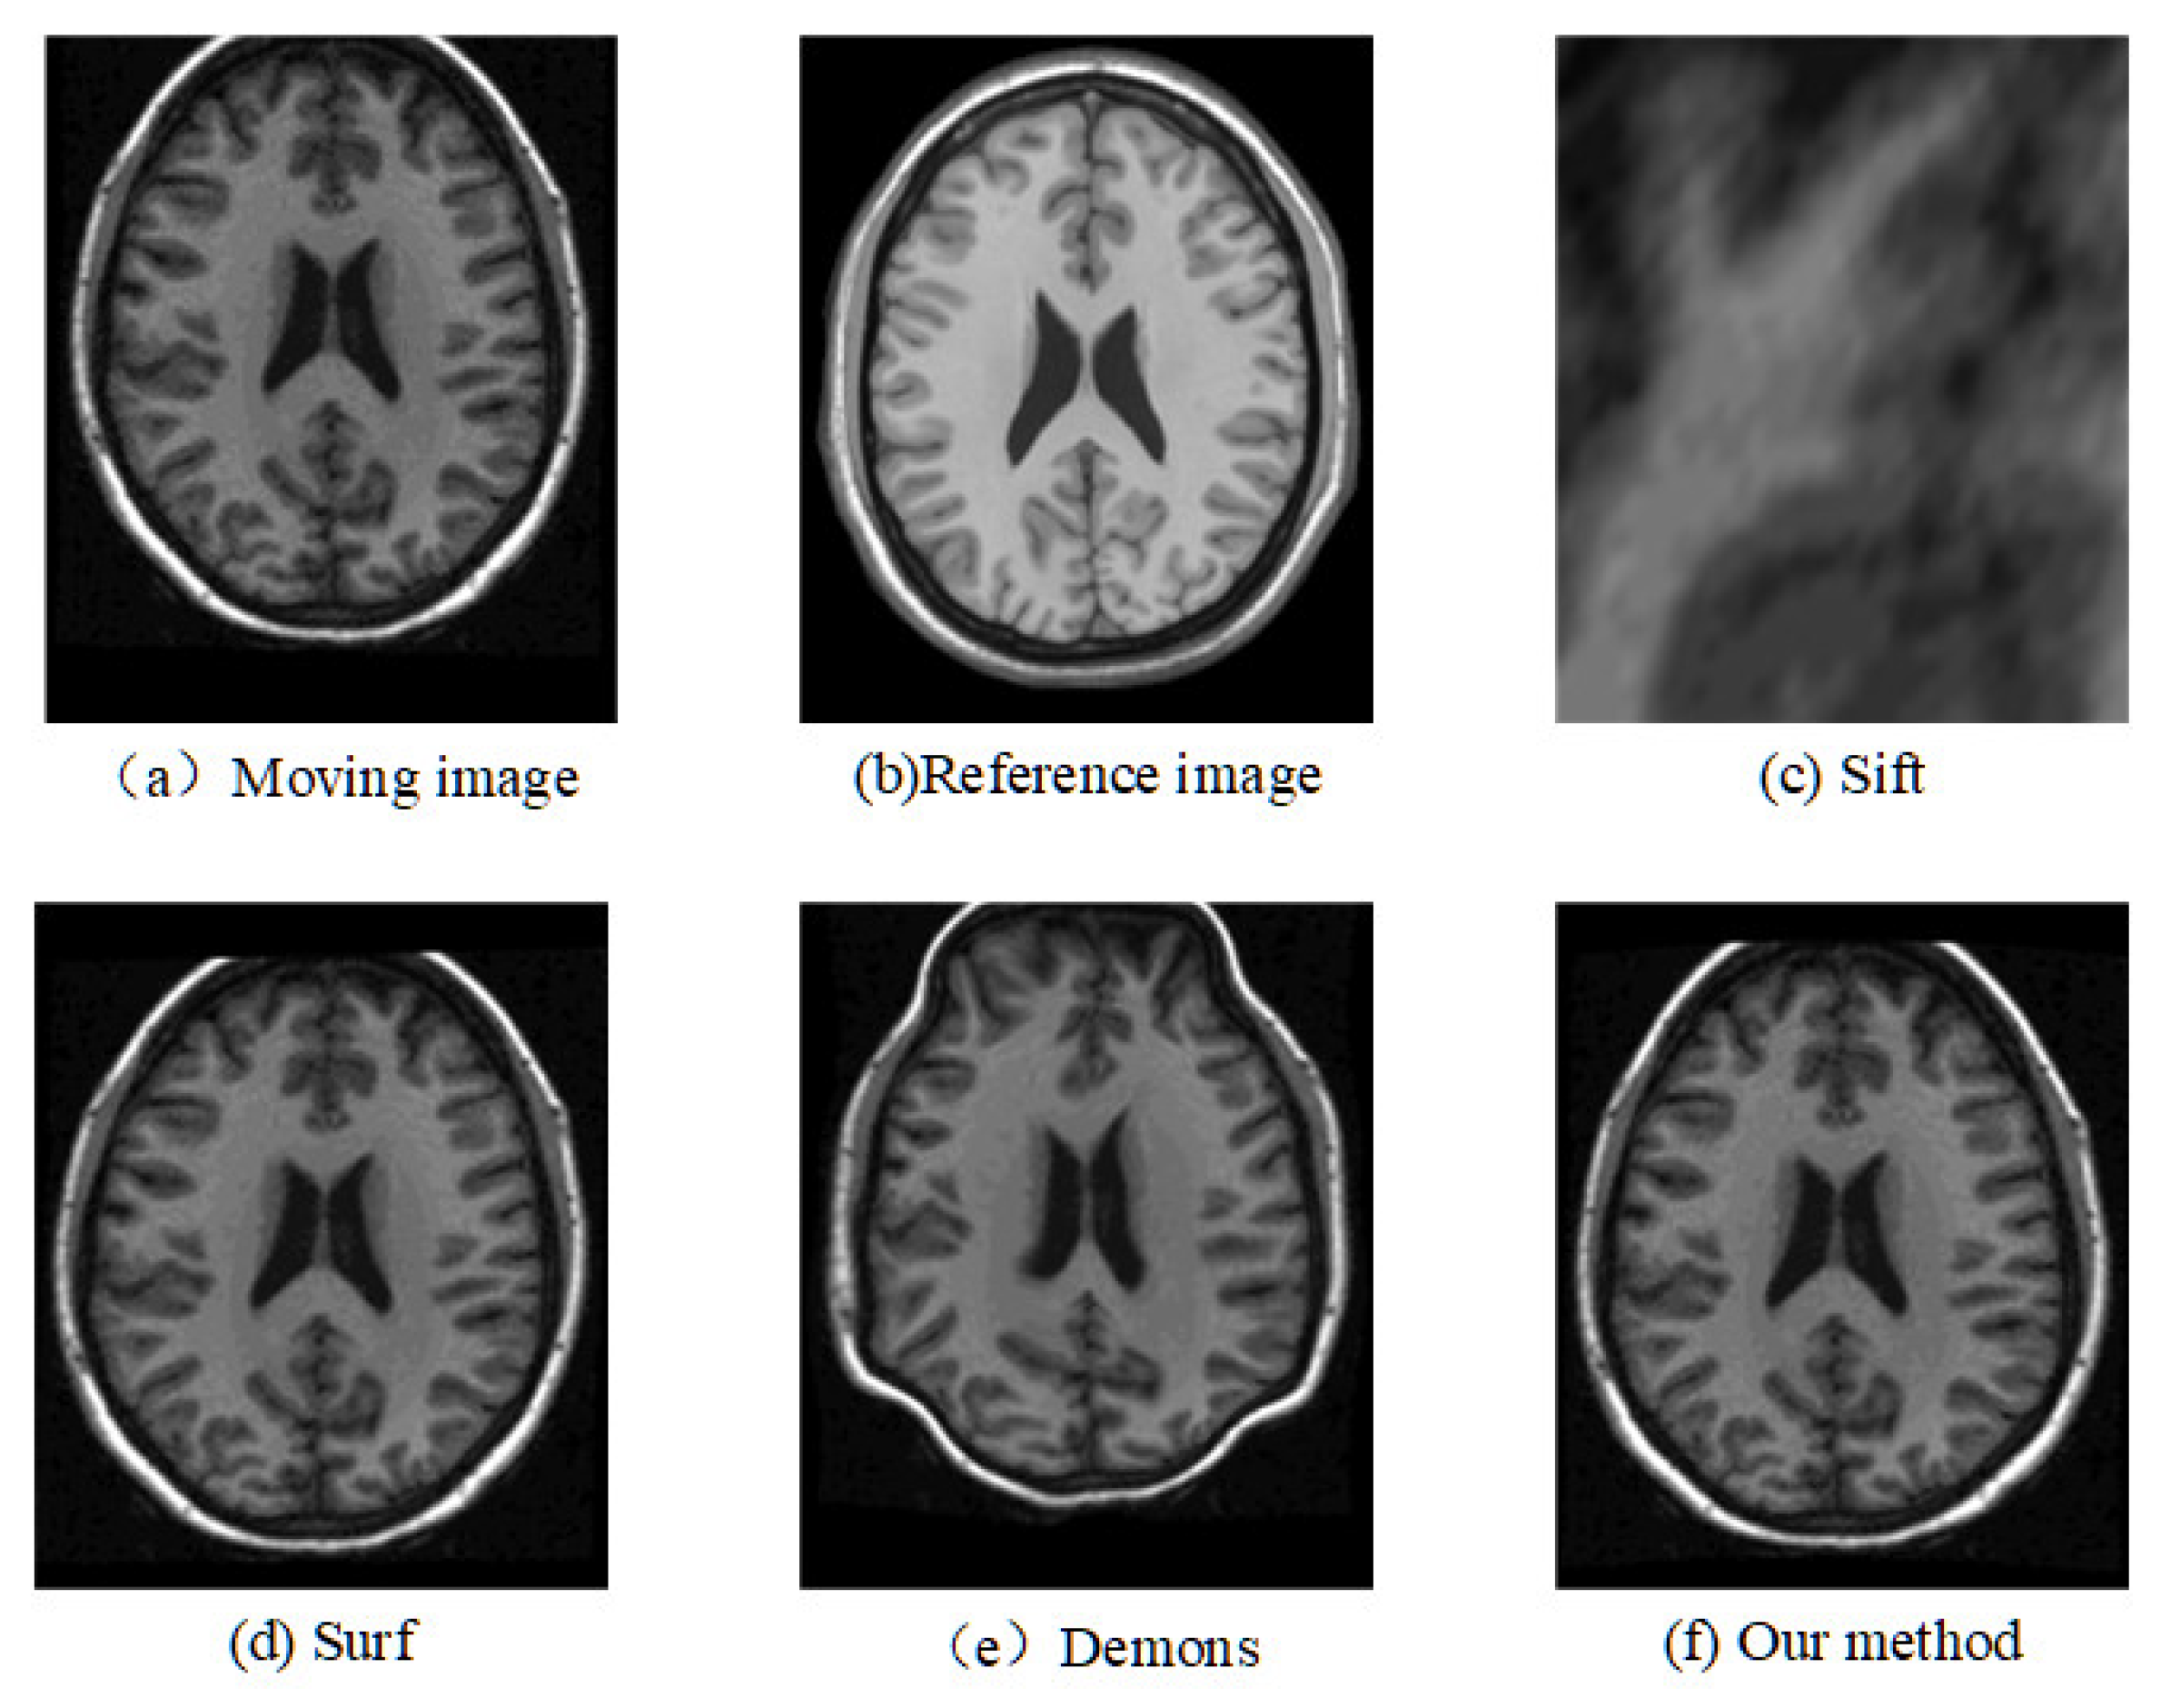

2. Materials and Methods

3. Results

4. Discussion